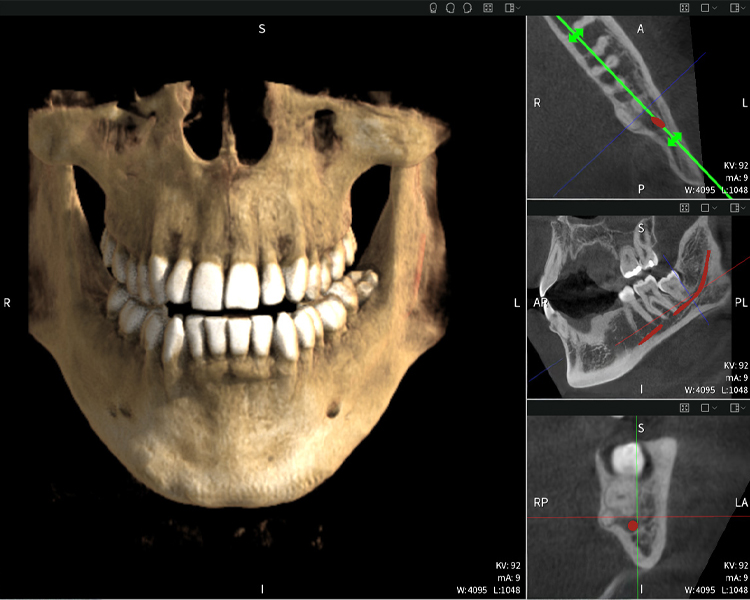

Figures b–d show various views of a 3D reconstruction of the mandible, providing a comprehensive overview of the mandibular anatomy, the position of the nerves in relation to the teeth, and allowing assessment of tooth symmetry and alignment.